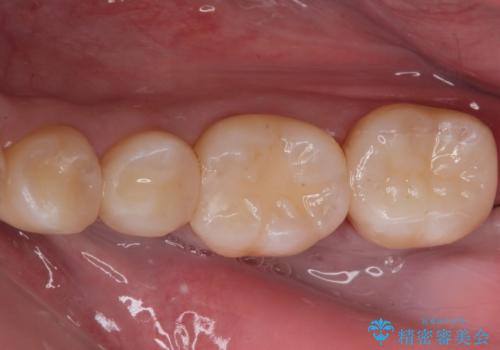

e-maxインレーによる治療

- 定期検診で来院してレントゲンを撮ったところ

歯と歯の間にう蝕ができていました。

拡大鏡下でう蝕を全て除去してe-maxインレーにて治療を行いました。

e-maxインレーは二次的にう蝕になるリスクが

銀の詰め物や樹脂の詰め物に比べて低いです。